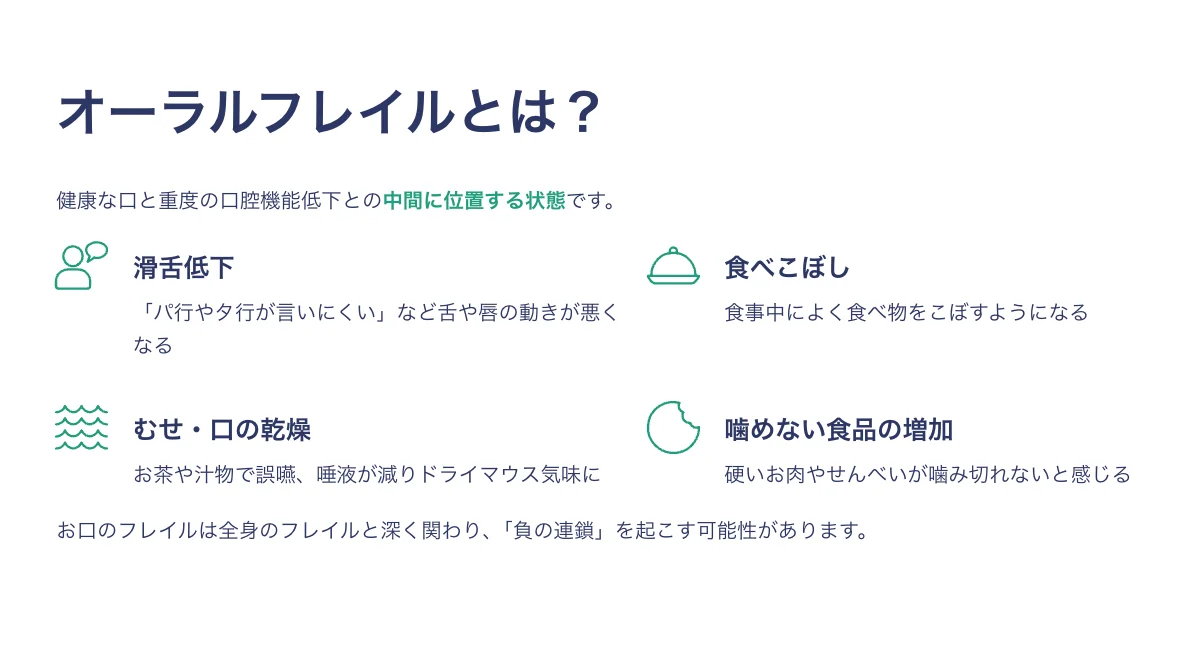

お口の衰えは万病の始まり?「オーラルフレイル」入門とセルフケア

オーラルフレイルとは、簡単に言うとお口の機能のちょっとした衰えのことです。 健康な口と、食べ物がうまく噛めない・飲み込めないといった重度の口腔機能低下との中間に位置する状態です。